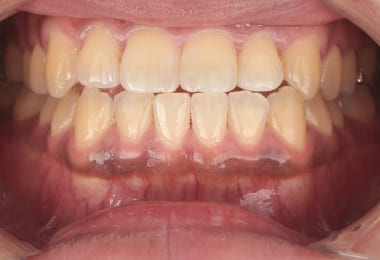

Before

2週間後

After